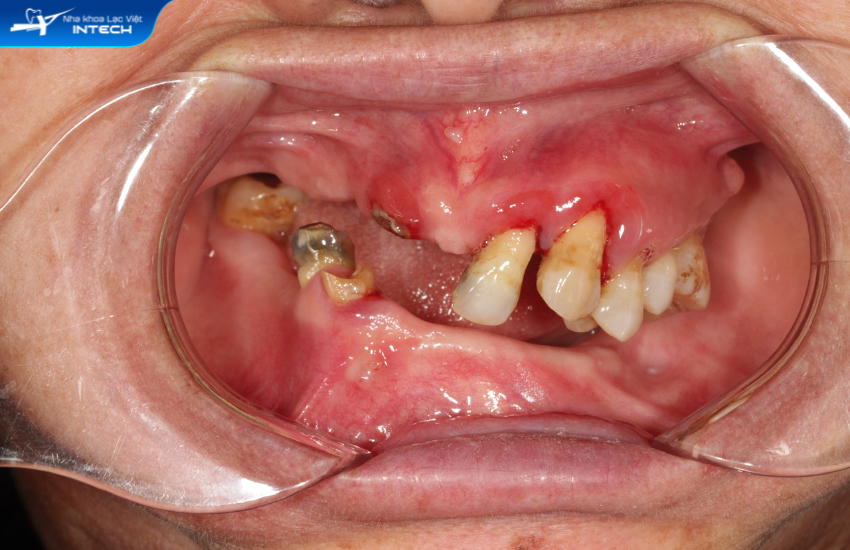

Tình trạng mất răng của Bộ trước khi đến với Lạc Việt Intech

Đau răng, mất răng không chỉ làm gián đoạn tới quá trình ăn uống, sinh hoạt của cô Bộ mà còn là nguyên nhân gây giảm sút sức khỏe trầm trọng. Từ hơn 20 năm nay, cô Bộ luôn chịu đựng những cơn đau răng khiến cô bị ê buốt dữ dội. Nhiều khi cơn đau kéo lên tới tận mang tai, đau dai dẳng cả đêm đã “cướp” đi giấc ngủ của cô.

Điều trị chính cho cô Bộ là bác sĩ Nguyễn Hoàng Dương - Chuyên gia cấy ghép implant tại Lạc Việt Intech. Sau khi thăm khám và dựa trên kết quả chụp phim CT Conebeam, bác sĩ Nguyễn Hoàng Dương chẩn đoán về tình trạng răng của cô Bộ như sau:

• Mất răng toàn bộ hàm dưới

• Hàm trên còn lại vài răng bị lung lay không còn chức năng ăn nhai

• Chức năng ăn nhai suy giảm